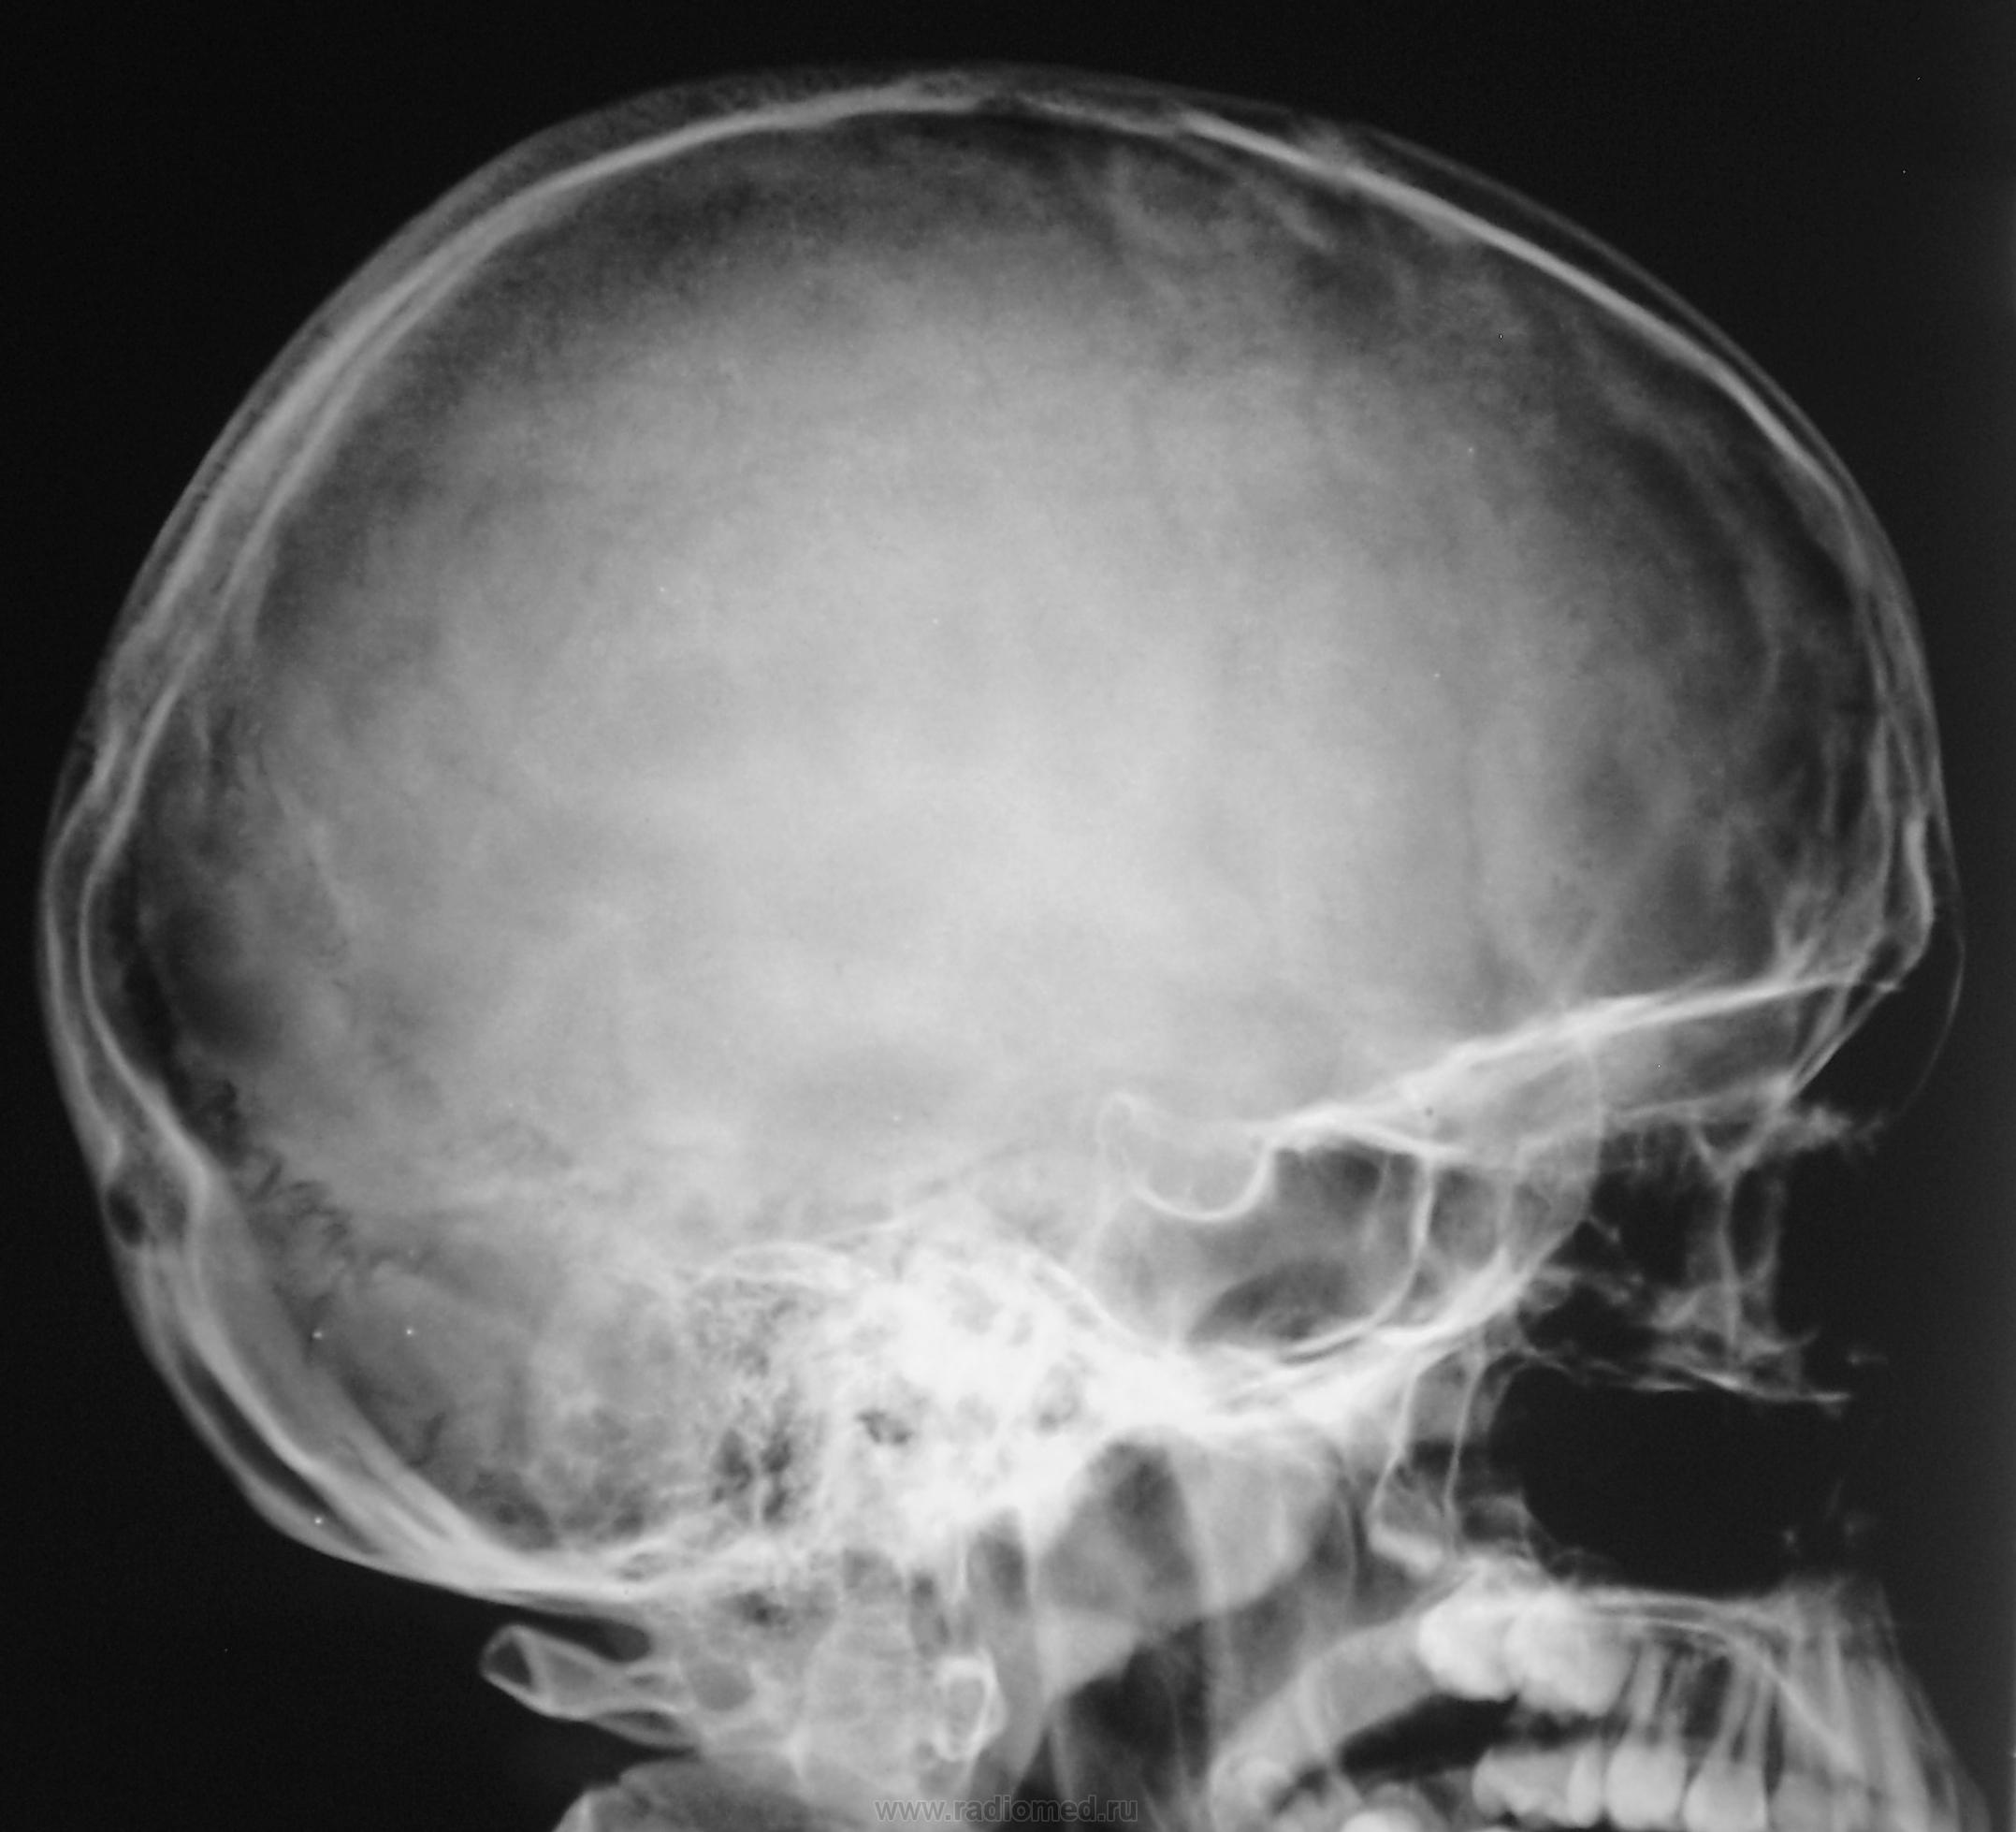

Рентгенография черепа и позвоночника: изображение и диагностика